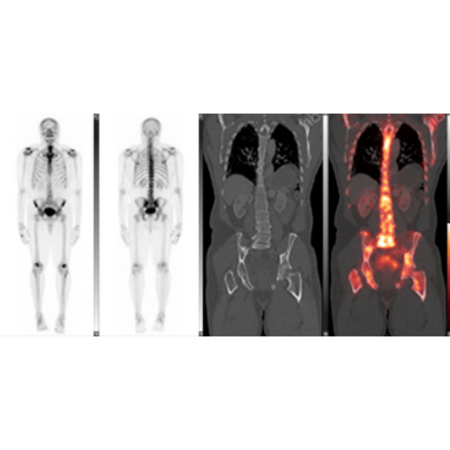

Quantitative Image Guidance

- Enables clinicians to make decisions with confidence.

- LesionID® supports the calculation of total tumor burden as well as individual statistics based on user-customizable cut-off criteria including PERCIST.

Advanced Therapy Response Tools

- Native support for Metabolic Tumor Volume, Total Lesion Glycolysis, and SUVpeak.

- Save time and add valuable information into your report.

Industry-Leading Auto-Segmentation Tools

- Provides accurate contours no matter who is doing the contouring.

- A gradient-based technique that detects the steepest drop off in SUV values to create the contour boundary automatically.

- Statistically more accurate than a common thresholding technique.